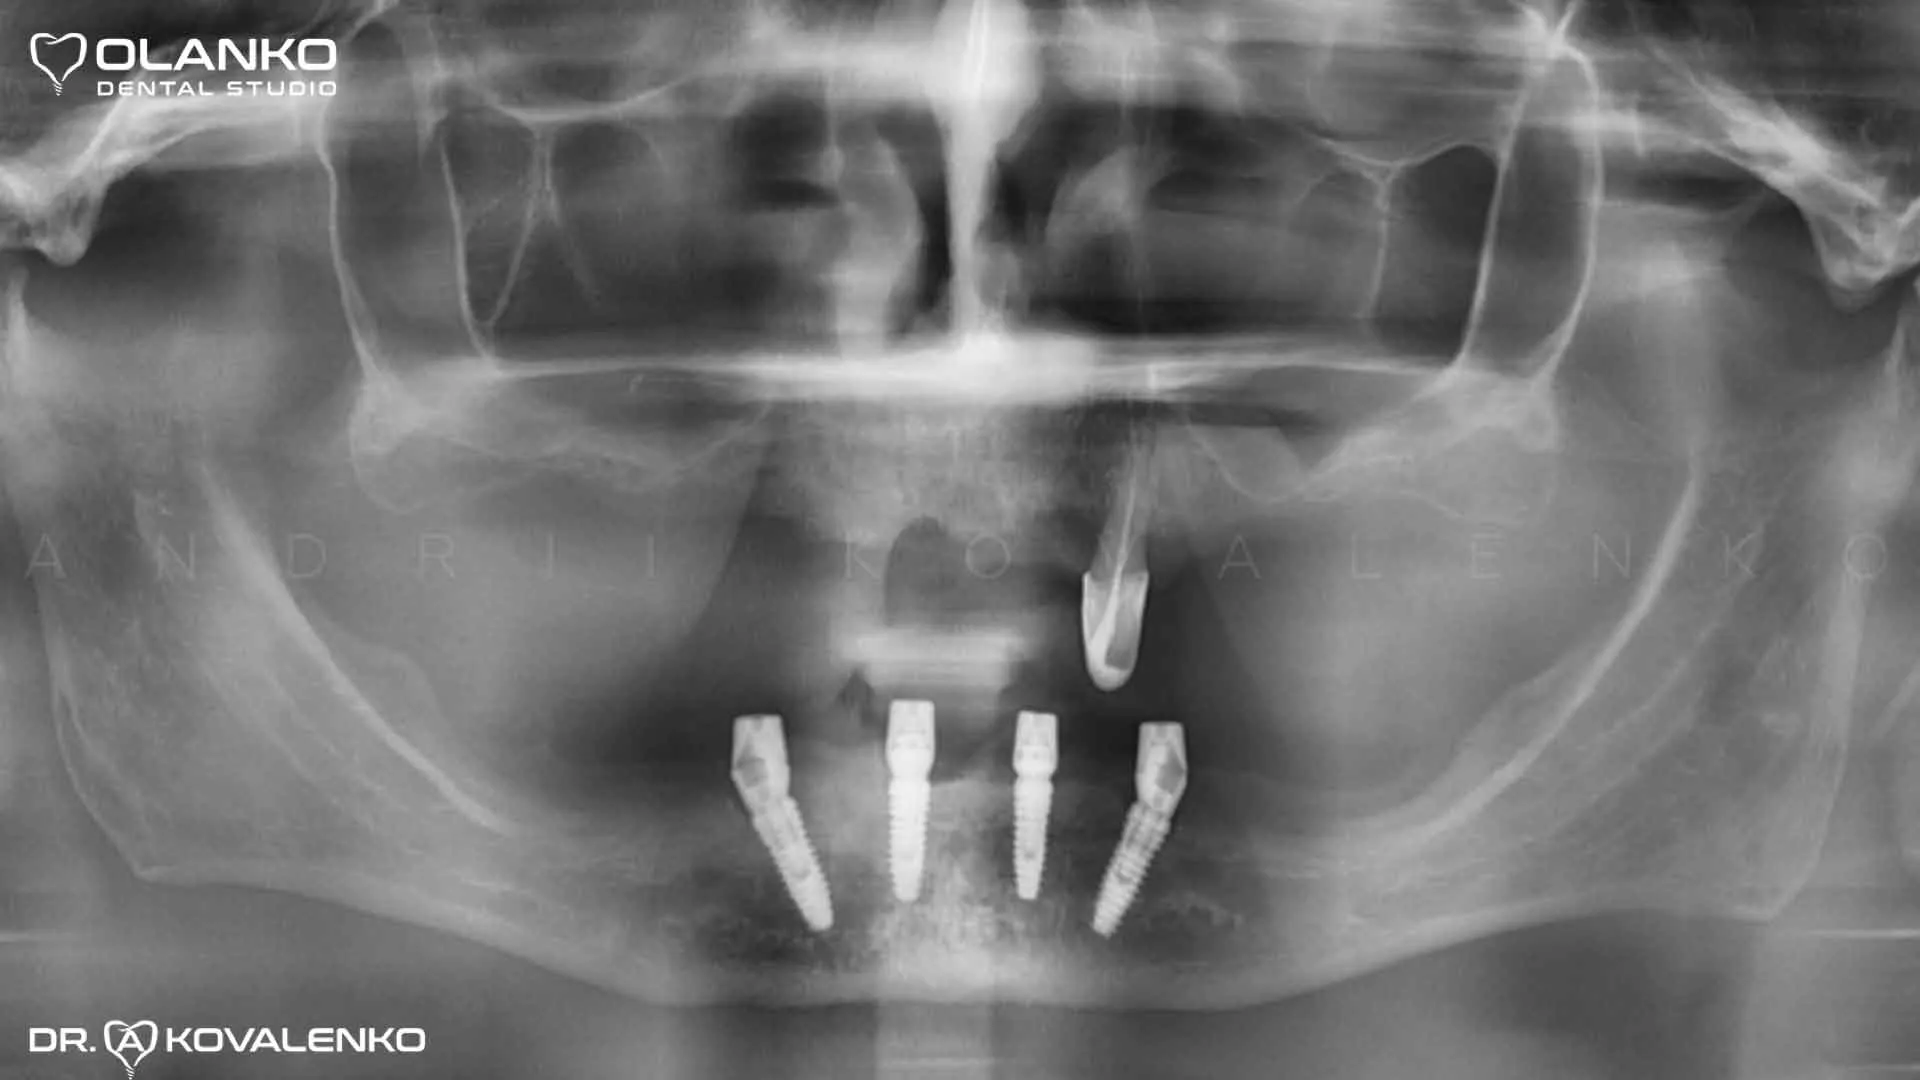

Компьютерное планирование операции по установке четырёх зубных имплантатов на нижнюю челюсть.

Изготовление навигационного хирургического шаблона для точной установки имплантатов в челюстную кость.

Установка четырёх зубных имплантатов.

Фото процесс установки зубных имплантов по шаблону

Клинический случай 9 имплантация зубов